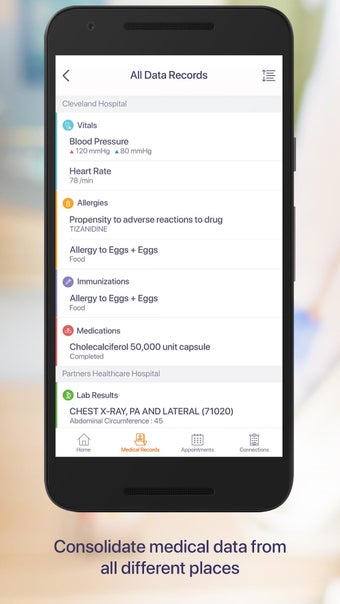

Carepassport là một ứng dụng Android cung cấp cho bệnh nhân một giải pháp toàn diện để quản lý dữ liệu y tế của họ. Ứng dụng cho phép bệnh nhân truy cập và lưu trữ an toàn dữ liệu y tế của mình, lên lịch hẹn, xem hình ảnh y tế, báo cáo xét nghiệm và lâm sàng từ các nhà cung cấp khác nhau, và chia sẻ chúng bằng công nghệ tính toán di động tiên tiến. Với Carepassport, bệnh nhân có thể dễ dàng quản lý nhu cầu chăm sóc sức khỏe của mình chỉ với vài lần chạm trên thiết bị di động của họ.

Một trong những tính năng quan trọng nhất của ứng dụng là việc truy cập dữ liệu y tế một chạm dễ dàng. Bệnh nhân có thể truy cập dữ liệu y tế của mình hoặc dữ liệu đại diện gia đình một cách an toàn và nhanh chóng, làm cho nó trở thành một công cụ tuyệt vời để quản lý lịch sử bệnh án của họ. Ứng dụng cũng cho phép người dùng tìm kiếm các phòng khám và bệnh viện gần đó, lên lịch hẹn, và thậm chí nhận chỉ đường đến cuộc hẹn của họ qua Uber. Ngoài ra, bệnh nhân có thể giao tiếp với nhà cung cấp chăm sóc của họ qua tin nhắn an toàn, chia sẻ hình ảnh y tế và cho phép thành viên gia đình truy cập dữ liệu y tế của họ thông qua cài đặt proxy an toàn. Cuối cùng, ứng dụng cung cấp tài liệu giáo dục liên quan đến chăm sóc sức khỏe và có thể kết nối với các thiết bị đeo được hoặc nhập dữ liệu y tế thủ công.